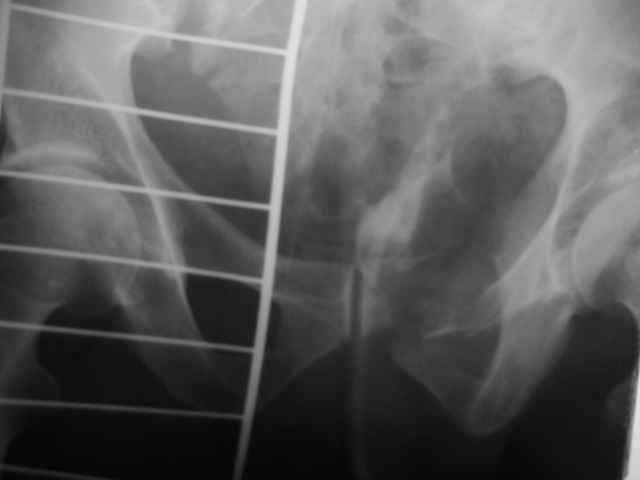

Выполнили операцию "желтому мужчине"(суррогаты так и продолжают пить)! С диагнозом:Перелом костей таза с нарушением тазового кольца

(перелом лонной ,седалищной костей справа .Разрыв КПС слева)Открытый (1 А Каплан) оскольчатый перелом проксимального эпиметафиза большеберцовой кости.

Сделали на 14 сутки остеосинтез б/берцовой кости мыщелковой пластиной LCP, остеосинтез костей таза АВФ(передняя опора, извинямси за качество R-грамм). Сохраняется смещение. Попытаемся его устранить этапно, но сомневаемся хватит ли жесткости АВФ и нет нигде меодики введения илиосакральных винтов!